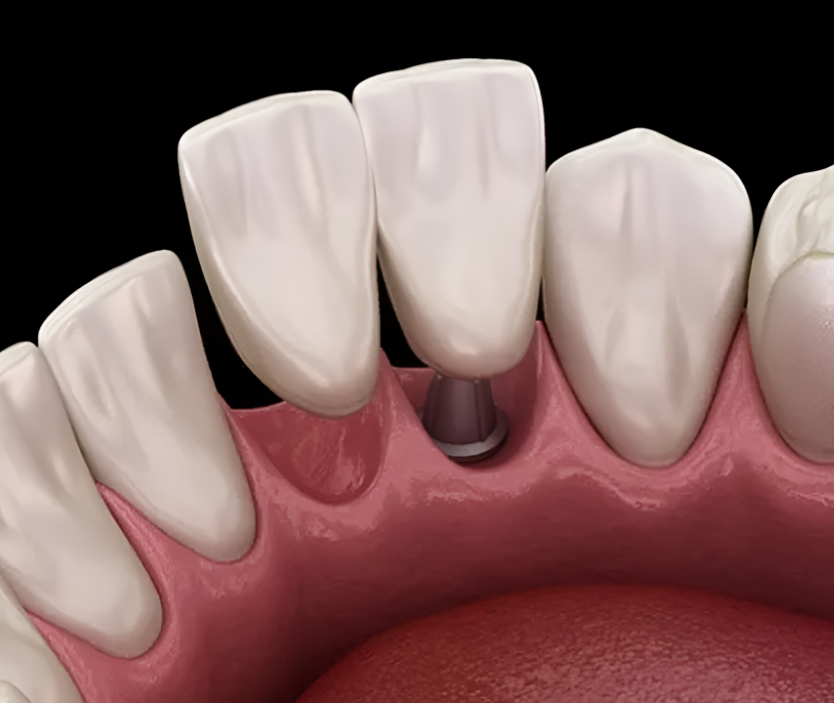

위와 같은 형태가 대표적인 ‘임플란트 브릿지’인데요. 치아 3개가 상실되었을 때, 2개만 심고 3개 치아 역할을 회복하는 모습입니다.